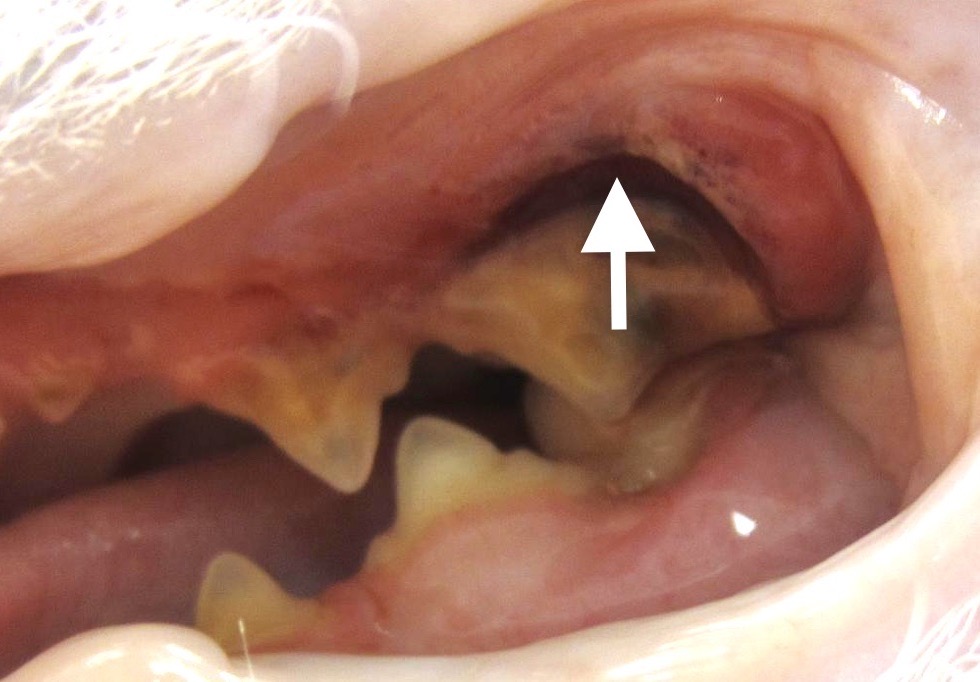

Bon, si on osait, on dirait que jusque-là, ça n’allait pas encore trop mal. (On a bien dit : si on osait). Les inflammations de la gencive et du parodonte sont bien embêtantes, mais restent à peu près localisées autour des dents atteintes ; si on ne traîne pas trop et qu’on met en place des soins dentaires et, si nécessaire, quelques extractions, on récupèrera le plus souvent une bouche saine. Le problème, c’est que le chat ne fait décidément rien comme tout le monde, et que l’inflammation peut, sous certaines conditions que nous détaillons juste après, gagner le fond de la bouche : c’est la stomatite caudale, encore appelée palatoglossite. (Glossite, c’est quand la langue est enflammée, et palato, c’est pour le palais). Et là, ça se traite beaucoup moins bien. Les photos ci-dessous montrent à quoi ça ressemble : on imagine ce que peut endurer le pauvre chat !

Bon alors là, c’est l’horreur complète, Hiroshima après la bombe. Pour ceux qui auraient du mal à s’y reconnaître, tellement c’est modifié, on a le chat en face de nous, bouche ouverte. En haut, c’est le palais, en bas, c’est la langue, de chaque côté on a les dents, et la cavité au milieu, c’est le passage pour les aliments. L’atteinte est symétrique, elle concerne tout le fond de la bouche (= stomatite caudale), en particulier l’arrière du palais, les piliers de la langue (ou piliers du pharynx), et la langue elle-même (= palatoglossite) et peut s’étendre à l’intérieur des joues. La photo de gauche a été prise chez un chat de sept ans, juste avant les extractions dentaires (on en parle plus loin, avec le traitement). À droite, la même en pire, chez une chatte Maine Coon de un an.